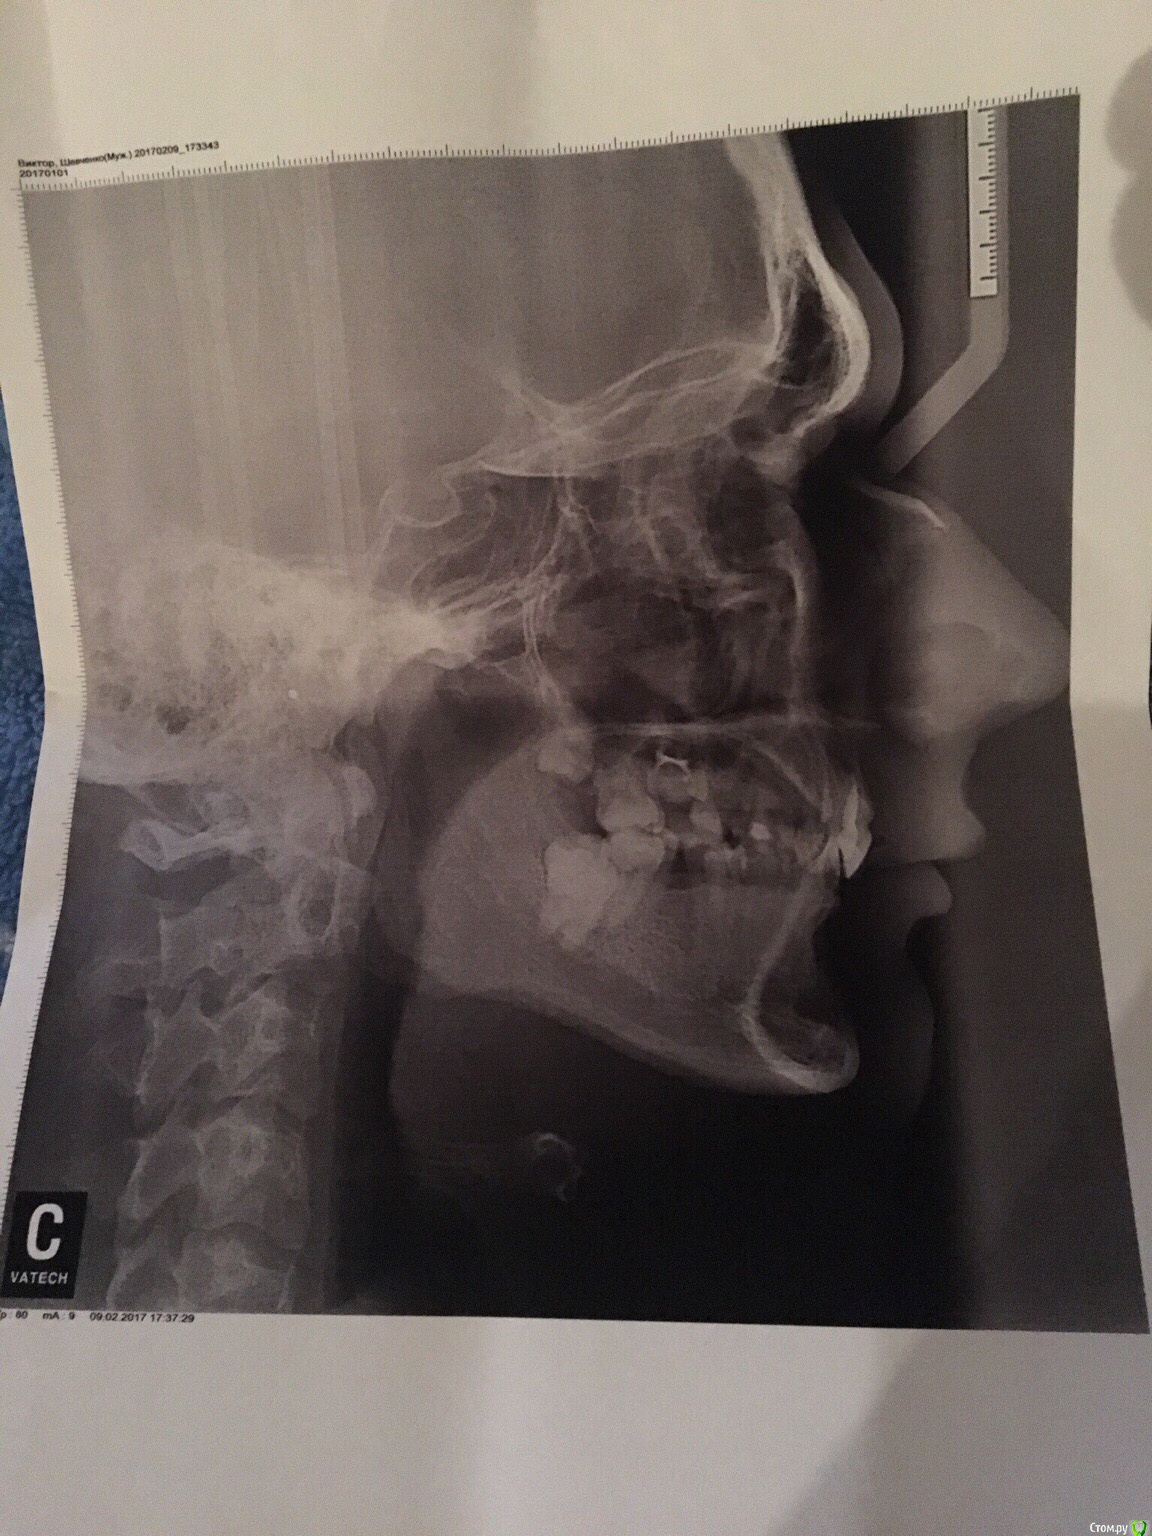

ViktorSh Опубликовано 21 июня, 2017 Поделиться Опубликовано 21 июня, 2017 Здравствуйте! Буду рад услышать мнение ортодонтов. Ситуация такова, мне почти 25 лет, пол муж, о наличии у меня неправильного прикуса узнал где-то с год назад и с того самого момента мне нет покоя, одни врачи говорят "да зачем тебе эти брекеты, сделай мост и делов то", я понимаю что можно поставить мосты, но при этом же будут затрагиваться здоровые зубы?! А у меня и так уже 6 зубов депульпированых (и это в 25 лет!!!) из них 4(!!!) передних на верхней челюсти... Другие врачи рекомендуют поставить брекеты, но точного плана действий, как и что я от них не слышу... В общем занимаюсь поиском "своего" ортодонта... Сейчас я санирую полость рта (на крайнем снимке мне лечат периодонтит на 7 справа). Если есть возможность, дайте мне понять примерную картину моей ситуации, что и в какой последовательности вы бы мне порекомендовали и что меня ждёт, буду очень вам благодарен, спасибо! Выкладываю все фото что у меня есть. Ссылка на комментарий

Yana guapa Опубликовано 22 июня, 2017 Поделиться Опубликовано 22 июня, 2017 Здравствуйте!... Другие врачи рекомендуют поставить брекеты, но точного плана действий, как и что я от них не слышу... В общем занимаюсь поиском "своего" ортодонта... а в чем вопрос? план лечения что, куда и как двигать вряд ли будут расписывать здесь.У Вас глубокий дистальный прикус (нижняя челюсть расположена глубоко по отношению к верхних зубам) и смещена кзади). Удалят все восьмерки (зубы мудрости), Будут исправлять форму верхнего зубного ряда, нижнего зубного ряда, а затем ставить нижнюю челюсть в правильное положение. На месте отсутствующих зубов поставят импланты. (это примерный план, как лечила бы я ) Ссылка на комментарий